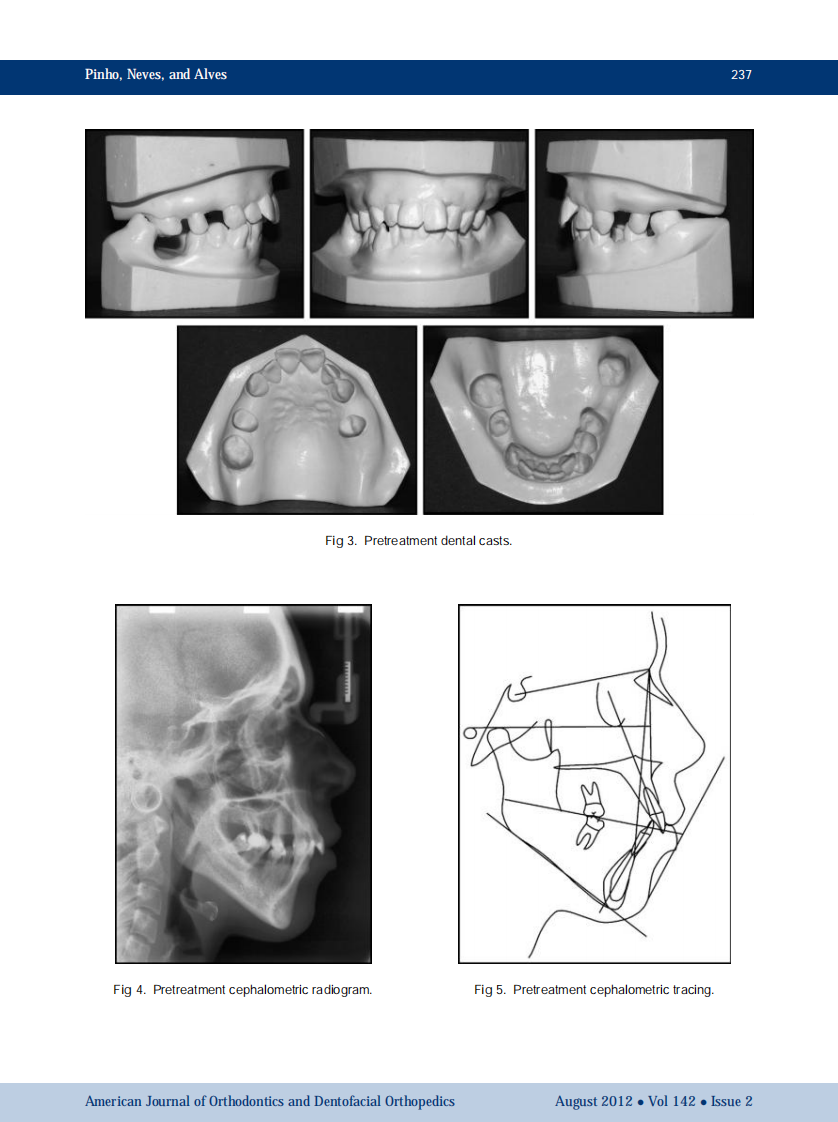

AJO-DO

1-s2.0-S0889540612004155-main.pdf